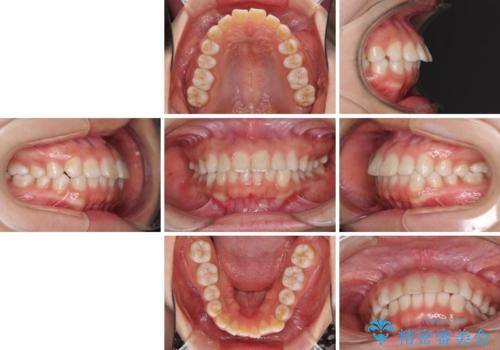

- 上の前歯の出っ歯を治したいとのことで来院された患者様です。

上下顎ともにIPR(歯と歯の間を削る)と歯列全体の拡大によって口元が引っ込むように設計し、インビザラインにより治療を行うこととしました。

どこまで口元を引っ込めることができるのか、患者様自身も正直分からない部分があったため、少しずつ治療ゴールを変更しながら仕上げていきました。

気になっていた前歯の飛び出した印象は、最終的にはスッキリと引っ込み、大変満足していただきました。